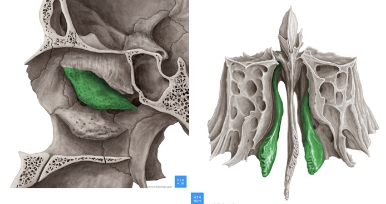

Cornete nasal superior

Cornete nasal medio

Laberintos Etmoidales

Forma cuboidea

Contiene los cornetes superiores y medios

Forma parte de la pared lateral de las fosas nasales

Contiene muchas cavidades neumáticas

Celdillas etmoidales, se dividen en anteriores y posteriores

Lámina papirácea en cara lateral